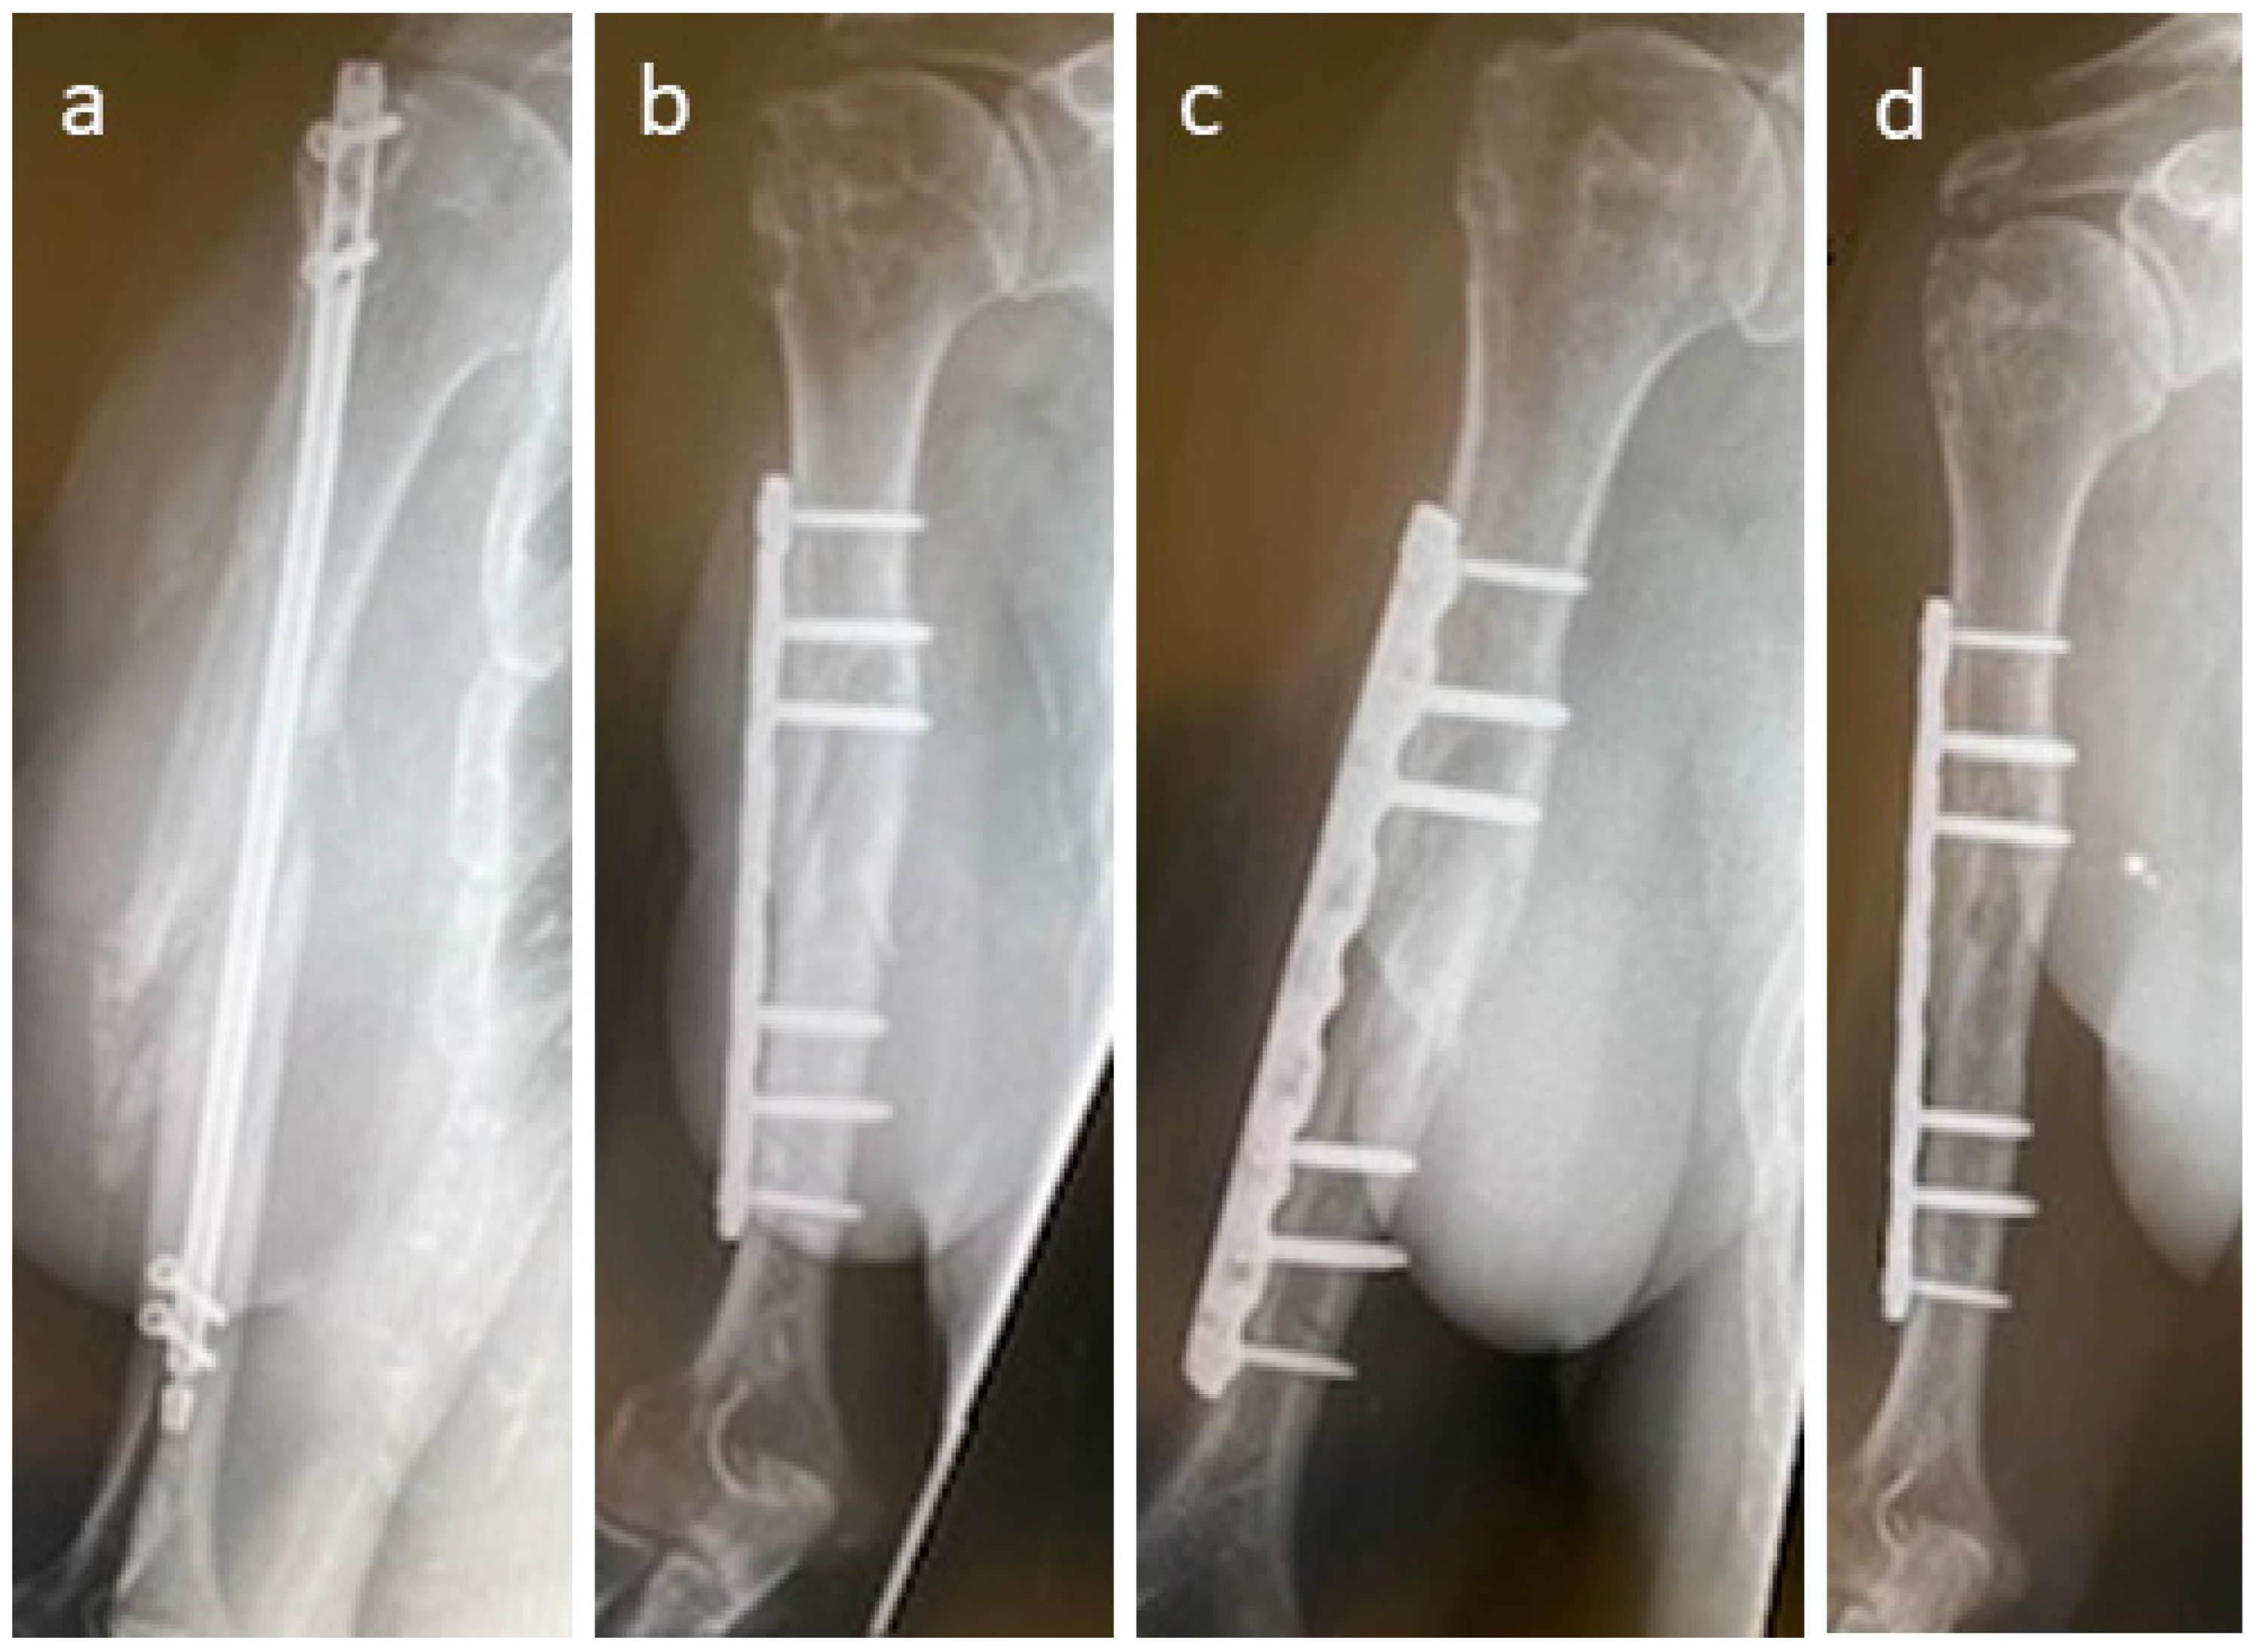

3.4. Selected Case Descriptions